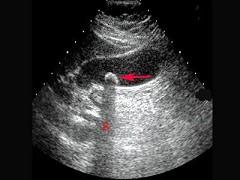

以下声像图显示?(?)A.振铃效应B.声影C.旁瓣效应D.部分容积效应E.镜像效应

问题 以下声像图显示?(?)

选项 A.振铃效应 B.声影 C.旁瓣效应 D.部分容积效应 E.镜像效应

答案 B